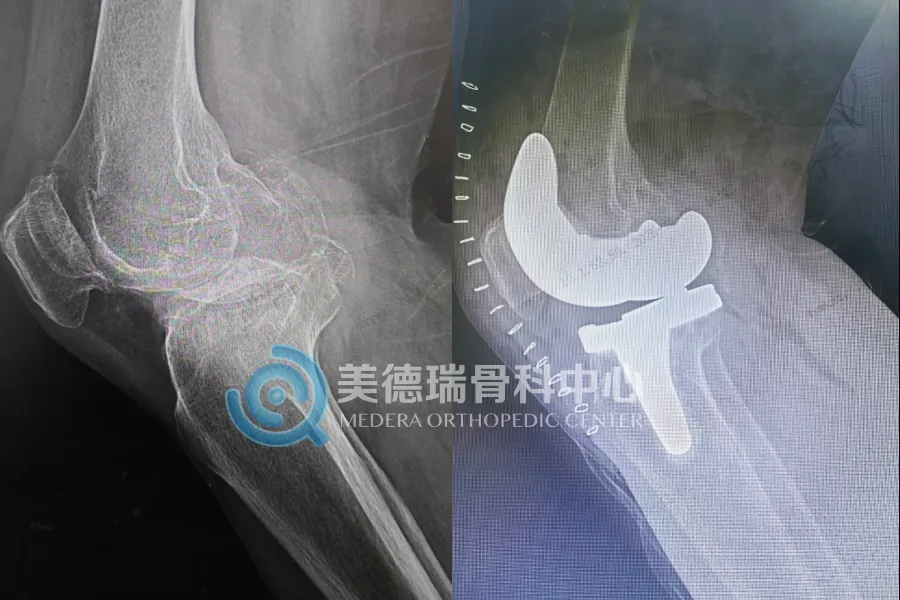

正如膝关节置换有“单髁”与“全膝”之分,髋关节置换手术也有其适配逻辑。对于高龄、对运动需求相对较低、身体机能较弱的患者,人工股骨头置换术手术时间更短、创伤更小、出血更少,能帮助老人以最快速度重新站立,规避卧床并发症。

董女士的手术方案正是基于此逻辑制定。团队没有盲目追求“全髋”,而是选择了更适合她身体条件和生活需求的股骨头置换。这不仅体现了对老年骨折处理的快捷与高效,更折射出中心在面对不同类型髋部损伤时,具备成熟的判断标准和多样的技术手段。